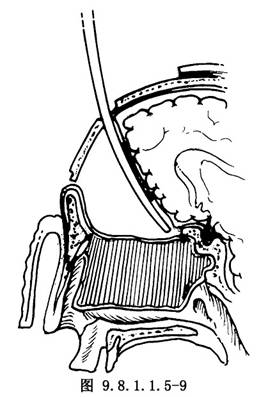

(1)顱腔術區關閉:清潔沖洗顱內術區,確實封閉硬腦膜裂口和缺損。製作額部腱膜瓣,蒂留於下方(圖9.8.1.1.5-8),由骨窗下緣轉入顱內,並於蝶骨平板和雙側眶板切緣處鑽孔縫合(圖9.8.1.1.5-9)。去除顱內敷料,大腦額葉復位,額骨瓣復位,鋼絲固定。復位額顳組織瓣,分層縫合(圖9.8.1.1.5-10)。前顱底缺損區,除硬腦膜修復外,又轉入了較厚的額部腱膜瓣,故骨缺損較小時可不作硬組織修復,但骨缺損區過大,則應用骨組織修復。